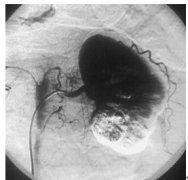

3.尿路平片及靜脈尿路造影顯示一側無腎影和不顯影,對側腎代償性增大,須注意排除其它原因所致的腎不顯影,如晚期腎結核、腎發育不全等。

4.腹膜後注氣造影、B型超聲及CT檢查顯示一側無腎。